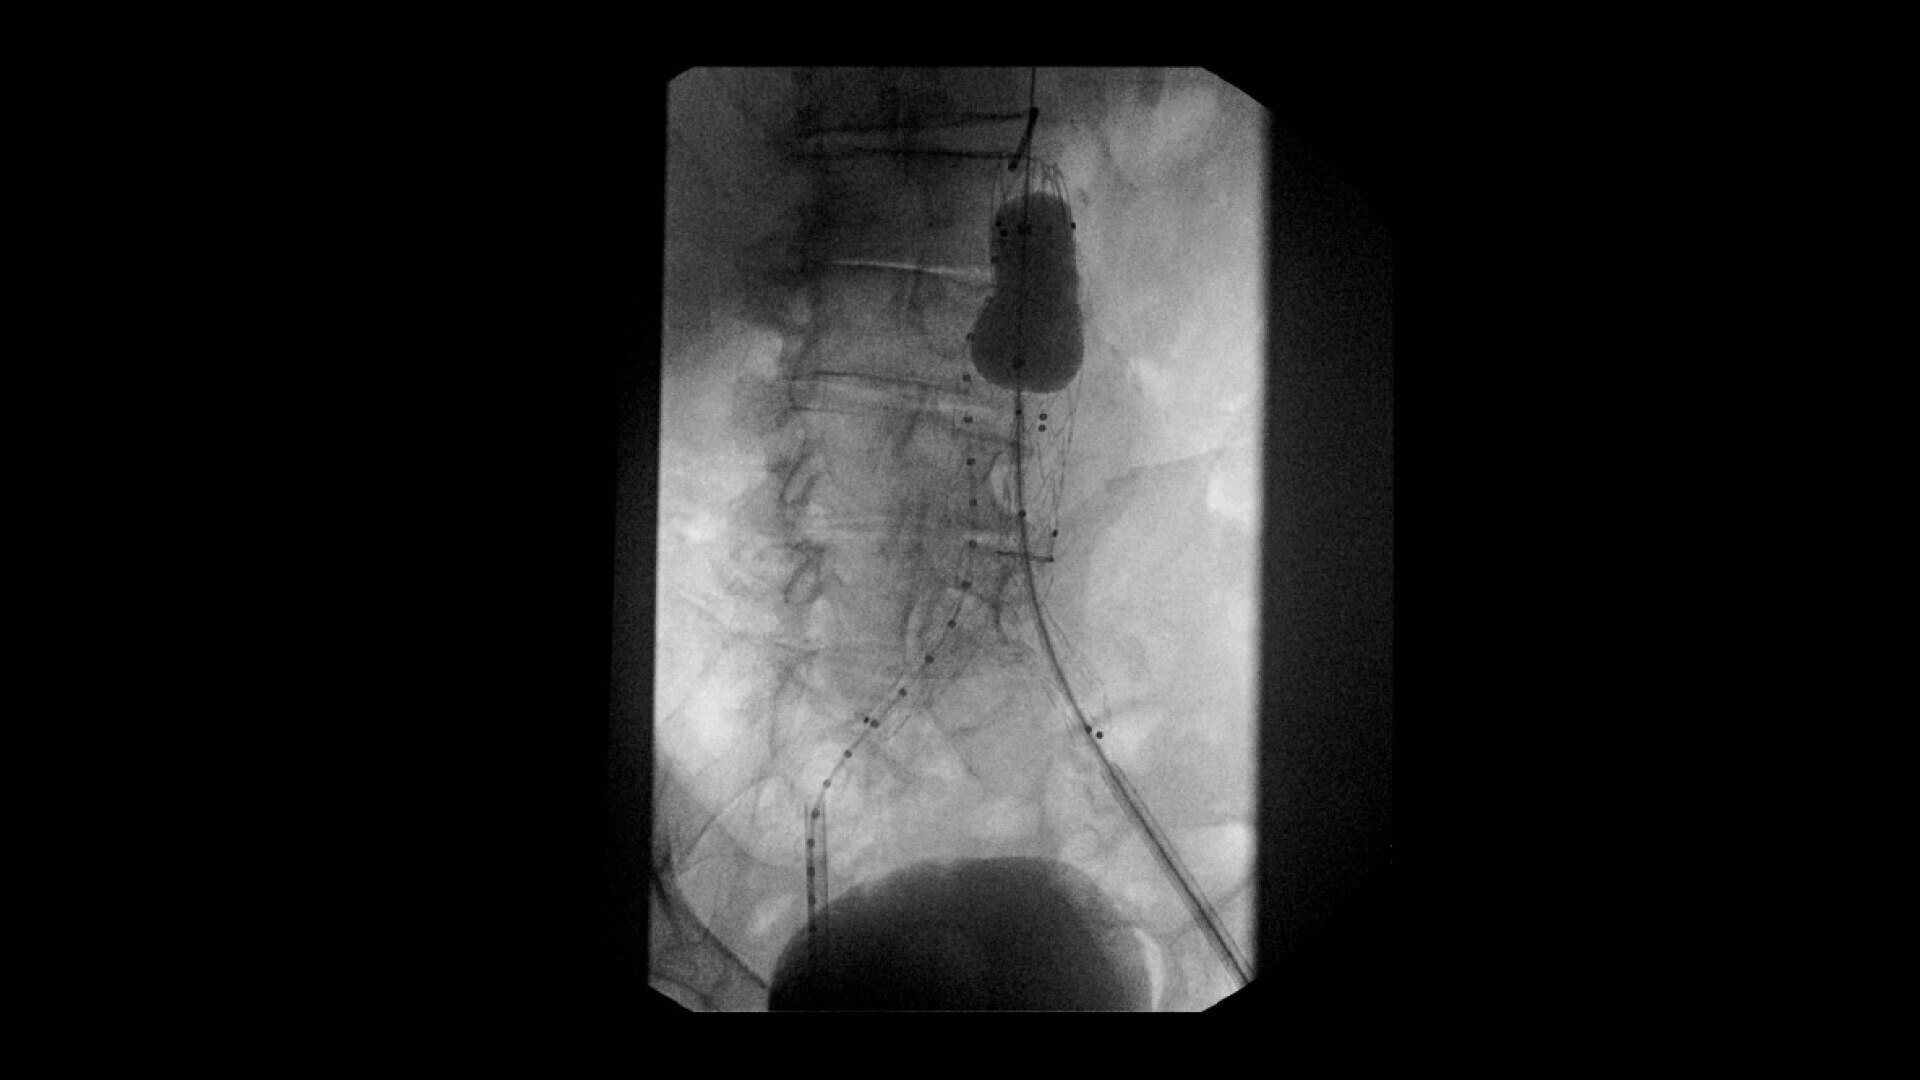

Perform a full leg Bolus Chase in one contrast run with a Preset Profile that includes Motion Tolerant Subtraction, that dynamically adjusts image quality based on presence of motion.

During contrast run-off procedures, easily select contrast type with positive (e.g. Iodine) or negative (e.g. Carbon Dioxide) during subtraction. The OEC Elite CFD cardiovascular package also includes Roadmapping.

Complex vascular procedures require powerful imaging systems. OEC premium C-arms perform in a variety of procedures such as:

•Abdominal aortic aneurysm (AAA) stent and balloon deployment

• Infrarenal aortic aneurysm repair

• Recanalization and stent placement in iliac arteries